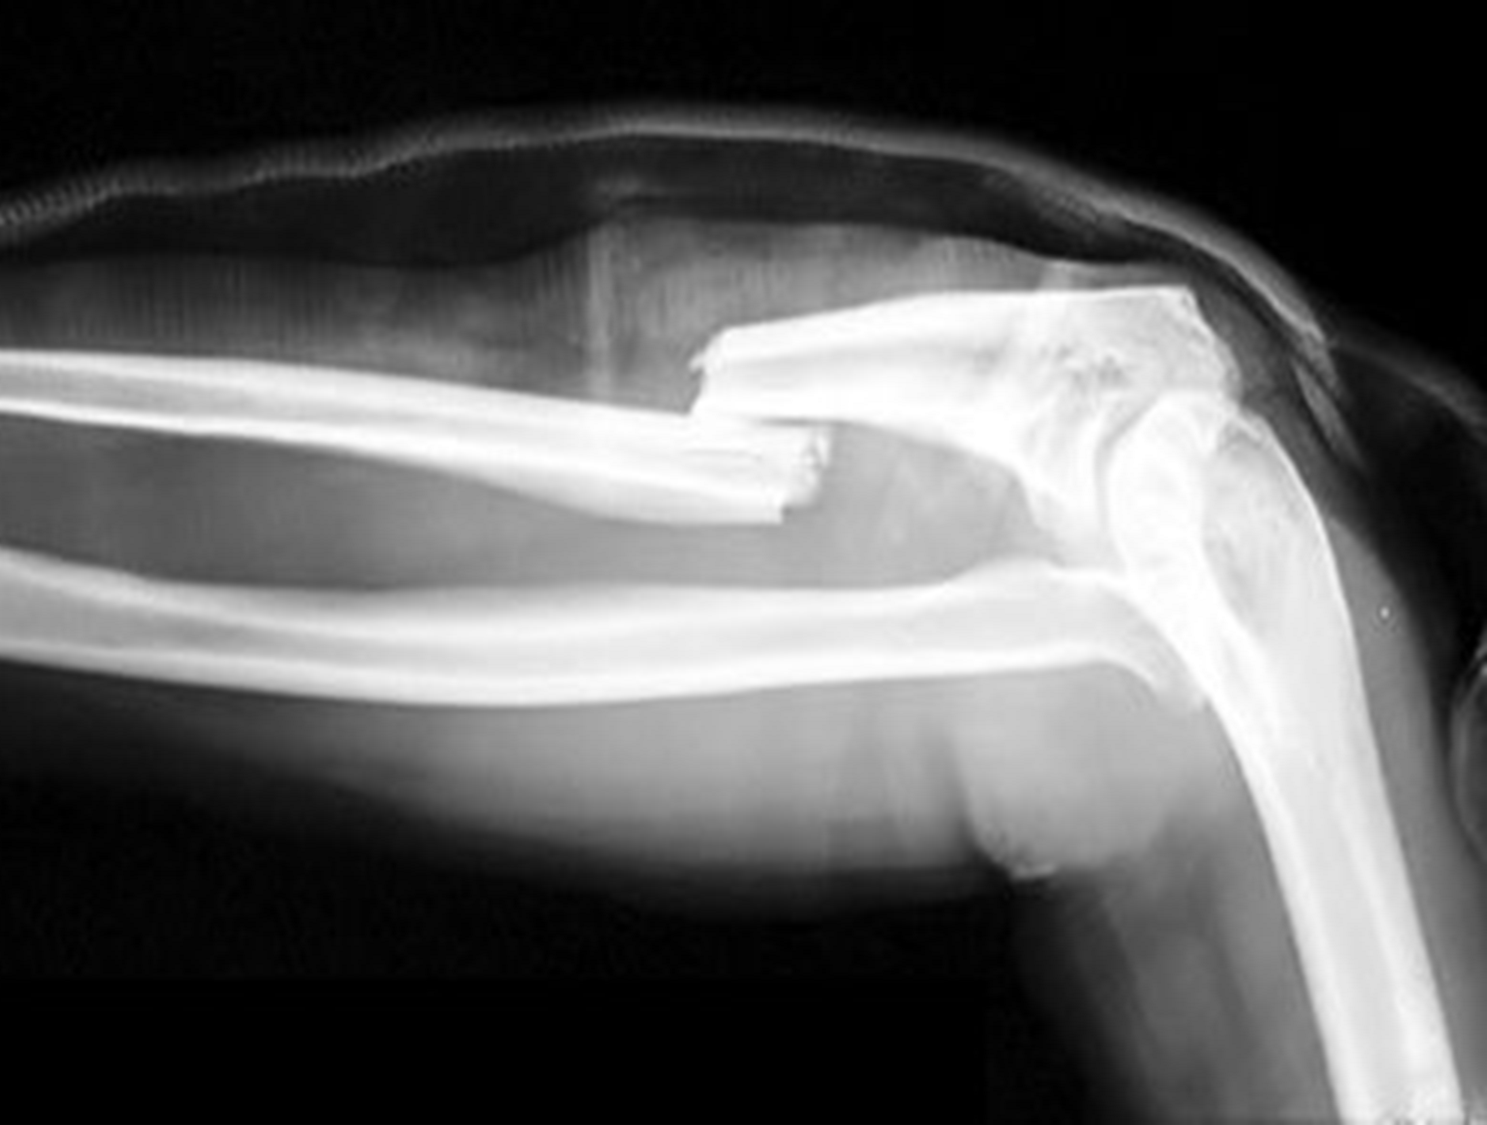

Displaced fracture

where a bone is broken and it does not align together correctly